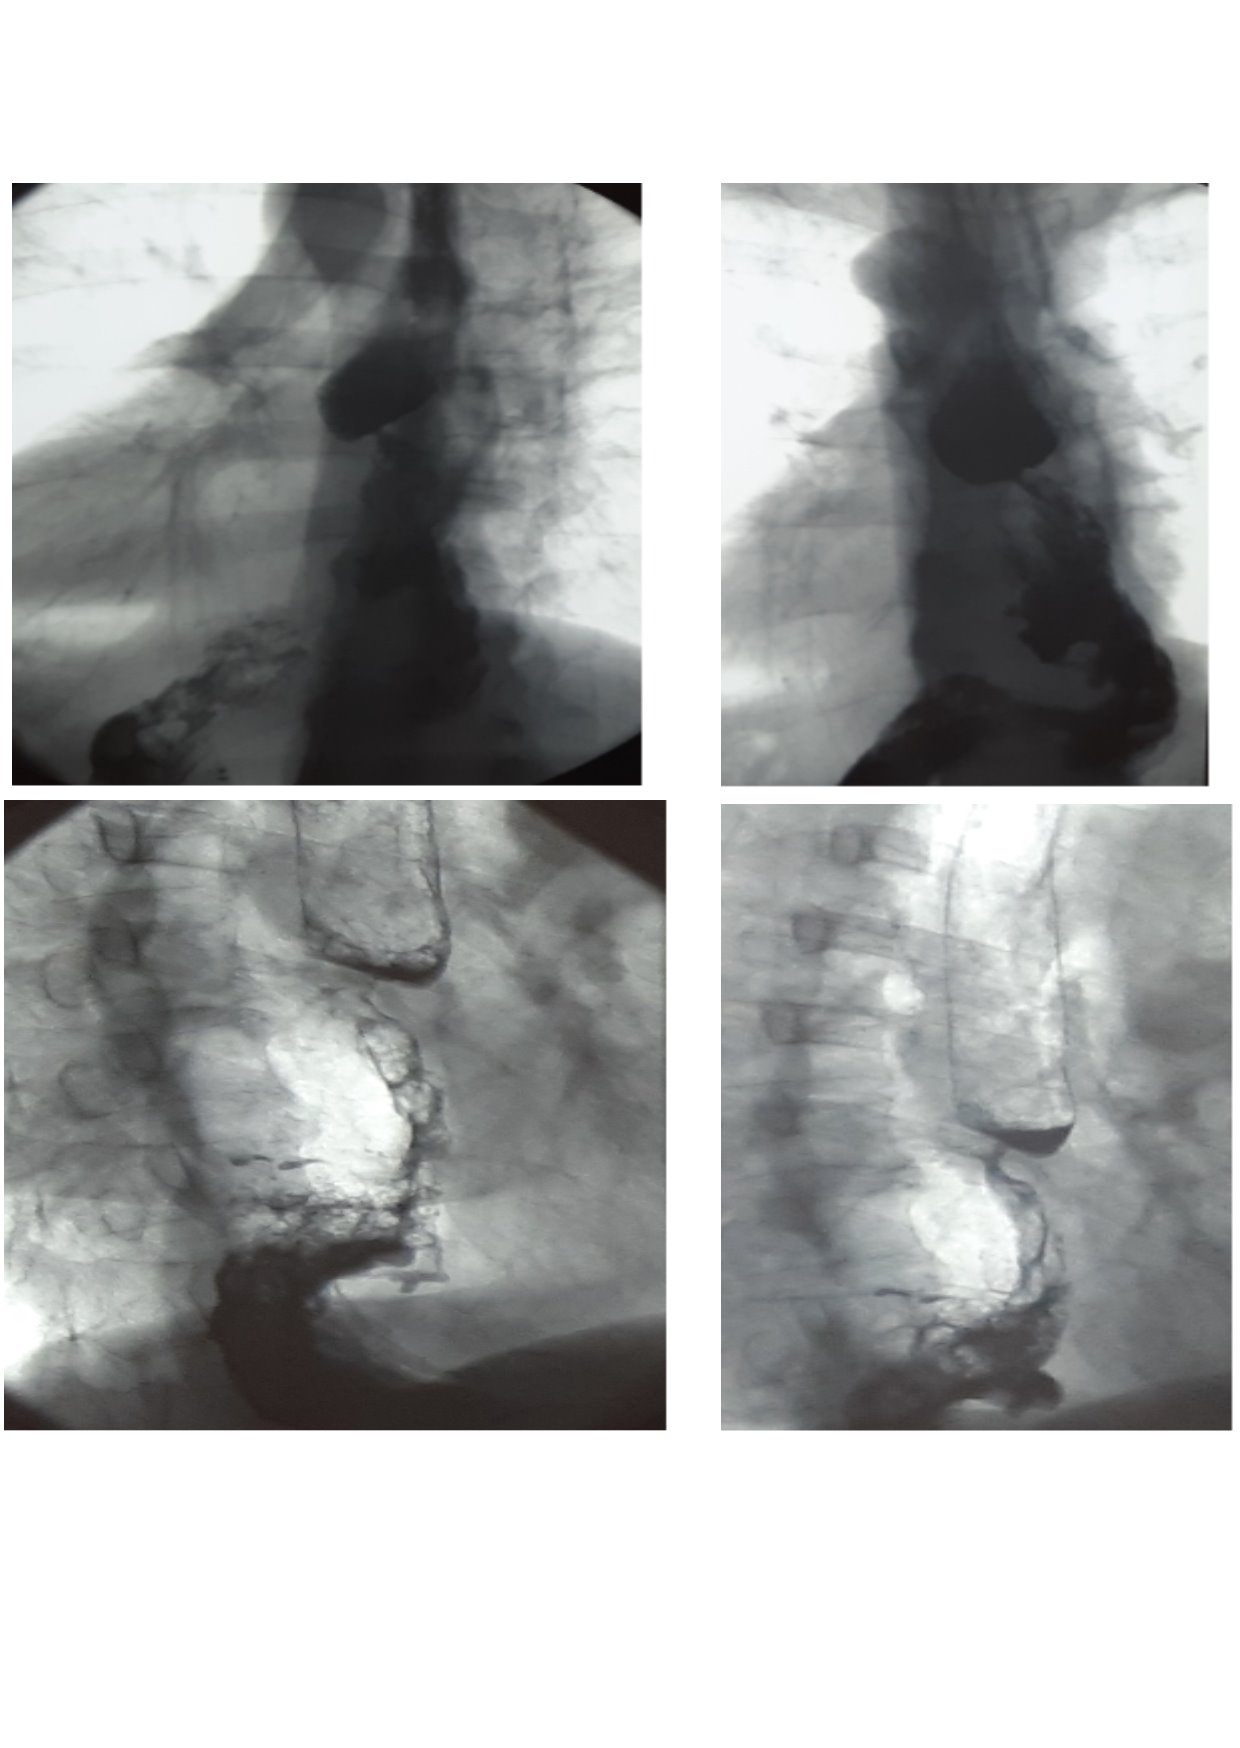

Endoscopic and X-ray examinations (Figure 3) revealed cicatrical stenosis in the zone of gastroanastomose. After per os intake of barium suspension, narrowing of the lumen to 0.4 cm along 0.7 cm length was determined in the region of anastomose in a series of X-ray pictures. Evacuation through the esophagus, transplant, a part of stomach in the abdominal cavity and duodenum was visible.

A course of gullet bougienage under X-ray control was conducted with a positive effect.

Fig. 3. Radiographic contrast examination of the esophagus and stomach in 4 months after surgery